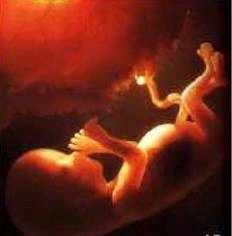

- Barnið hefur nú náð um það bil þriðja hluta af væntanlegri fæðingarþyngd.

- Það vegur u.þ.b. 1150 gr og mælist 25 sm í sethæð.

- Fætur mælast nú næstum 5,5 sm.

- Hárin á höfðinu eru orðin hlutfallslega löng.

- Barnatennurnar undir gómnum eru myndaðar.

- Nú hefst síðasti þriðjungu meðgöngunnar og það markar ákveðin þáttaskil. Hjá hluta kvenna fer róðurinn að þyngjast og ýmis vandamál sem tengjast vaxandi fyrirferð og þunga geta gert vart við sig. Lífsstíll hinnar verðandi móður skiptir þar sköpum.